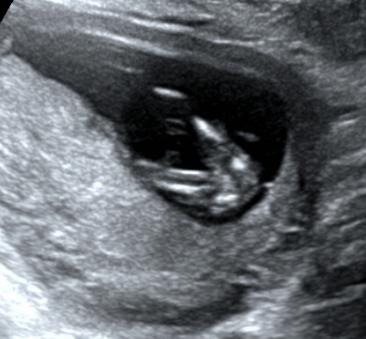

当然,这个时期我们除了重点观察TA的肢体以外,此时需要重点关注NT。

NT测量一般在11-13+6周内进行。

此时测量彩具有参考意义,但测量NT完全看宝宝的心情。

因为TA 有时候真的很不给面子。。。

比如:

有这样趴着的;

还有倒立的

还有直接给个背影的。。。。